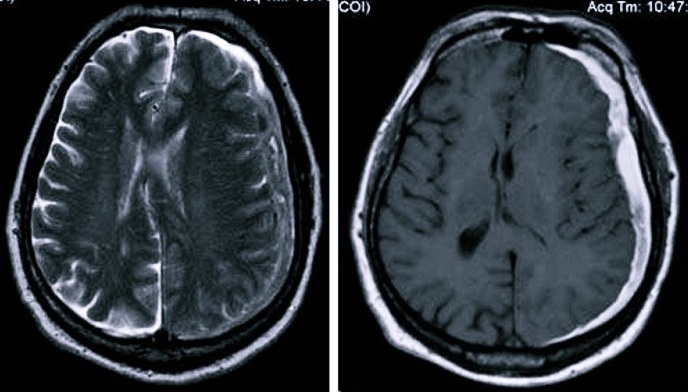

Основными причинами травматического субдурального кровоизлияния является травматизация головного мозга и повреждение интракраниальных вен. Важнейшими диагностическими элементами являются КТ и МРТ, причем современные специалисты больше предпочитают компьютерную томографию, с помощью которой быстро обнаруживается однородная серповидная зона увеличенной плотности.

Если для диагностики выбрана МРТ, то зачастую назначается проведение процедуры с контрастом, что хорошо помогает установить точный диагноз и получить дополнительную информацию в особо сложных случаях.